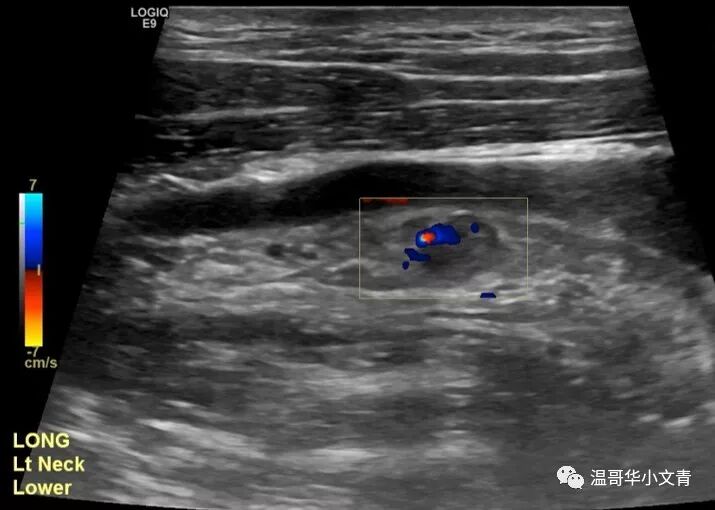

随着知识的普及,大家都知道颈部彩超检查对于甲癌病人非常重要,尤其是乳头状癌和髓样癌的病人。 经常有病友来群里吐槽: “他奶奶的,排队排了两个小时,彩超医生把探头在我脖子上晃了40秒就搞完了,真尼玛瞎搞!” “做了几个医生的彩超,各个结果都不同,真蛋疼!” 所以今天小编就和大家来讨论下彩超检查: 如何正确的进行彩超检查? 如何解读彩超结果? 彩超检查的结果有什么意义? 如何正确的进行颈部彩超检查? 这部分内容取自斯坦福医院的Lisa Orloff,她本身是头颈外科医生,也是彩超师。 术前彩超和术后彩超的操作方式是类似的。不过,术前彩超是越精确越好,术后有时候对彩超的要求反倒不需要那么高,今天主要讨论的是术前彩超。做彩超最重要的是动图,通过动图发现可疑的病灶,再逐个详细分析。Lisa推荐的检查顺序是: A 甲状腺和气管旁中央区淋巴结 (两侧) B 峡部气管前中央区淋巴结 C 喉前中央区淋巴结和声带 D 侧颈大血管周围二三四区淋巴结 (两侧) E 侧颈五区淋巴结(两侧) F 一区淋巴结以及唾液腺 当动图发现了问题之后,再把有问题的地方详细的记录下来,形成一整套图片。最后彩超医生把图片和报告交给内分泌医生或者手术医生,由他们定夺治疗方案。彩超最重要的其实是动图和图片,而不是报告上简单的几行字。 彩超结果能解读出哪些信息? 第一个是判断甲状腺结节的大小,数目和属性。如果甲状腺的结节出现微钙化,纵横比大于一,边界不清晰这些字眼,结节是恶性的可能性就比较高。一般来说拿到图片良恶性都能有个大致判断,有的时候不好判断也没关系,反正还有穿刺。 第二个是如果是甲状腺癌,判断原发肿瘤有没有侵犯周围的组织。比如说这个肿瘤是不是和气管的关系比较密切?是不是有可能侵犯了前被膜?是不是有可能侵犯了后被膜导致和喉返神经关系密切。 第三个是判断淋巴结的转移情况。大家都知道如果淋巴结出现钙化,囊性化,局部高回声基本都是转移的;如果没有淋巴结门结构,形状是圆形那么就是相对可疑的。读图比看文字描述更可靠!因为你会知道这个淋巴结到底有多可疑!或者到底有多坏! 实际上彩超在侧颈淋巴结的区域更为敏感,下面就是一些例子: 右侧颈5区的淋巴结,8毫米,不规则血流。红箭头指向的地方是微钙化,你看图就知道这是乳头状癌的转移淋巴结。 左侧颈4区的淋巴结,6毫米,不规则血流。高度怀疑是转移的淋巴结。 左侧颈3区的淋巴结,7毫米。红箭头指向的地方是钙化点,你知道这是一个乳头状癌转移淋巴结。 左侧颈2区的淋巴结,1.5厘米,没有明显的淋巴结门结构,是一个中度可疑的淋巴结。 当彩超医生阅读完所有的图片之后,就会把信息聚集起来,形成一幅肿瘤分布图,告诉内分泌或者外科医生原发肿瘤到底有多少?腺外侵犯有多少?淋巴结转移有多少?它们在哪里? 彩超检查结果有什么意义? 第一,彩超结果可以指导医生是否需要进一步的影像学检查,比如说颈部的增强CT。 大概有20%-25%的病人在彩超上有明显的转移需要颈部增强CT检查。彩超能看出来结节和气管关系密切,但是要想知道侵犯了气管的多大面积就需要增强CT;彩超能看出来常规的中央区侧颈区的淋巴结转移,但是有的病人可以转移到鼻子后面的淋巴结(咽后淋巴结),胸骨后面的淋巴结(纵隔淋巴结),这时候就需要增强CT。 第二,彩超结果可以指导放射科医生穿刺哪些部位。 一般来说,需要一个恶性证据去展开手术;另外可能影响手术方案的淋巴结也需要穿刺。 第三,彩超结果可以指导手术医生手术的方案。 手术是半切还是全切? 中央区清扫是一侧还是两侧? 侧颈区清扫不清扫,清扫多大的范围? 手术涉及不涉及气管,食道这些关键位置? ...... 第四,彩超结果可以告诉病人大概的预后。 很多人拿到彩超结果还没手术就喜欢问需要不需要碘131?有没有远转?这个确实需要一步步的来看,但是彩超的结果也是一个很好的预判。 如果你的彩超检查很详细但没有显示任何转移,你的预后是非常非常好的,你基本不可能发生远处转移,而且术后需要碘治疗的可能性很小;如果你的彩超显示有大面积的淋巴结转移,你术后基本就需要碘治疗,而且可能还需要一个胸部CT评估肺部的状况。